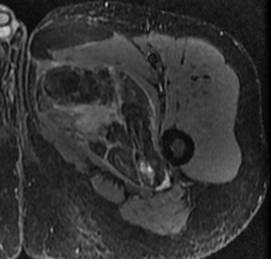

Liposarcome bien différencié. Noter la masse graisseuse, ayant une composante tissulaire (flèches) et des septas épais rehaussés après injection de gadolinium